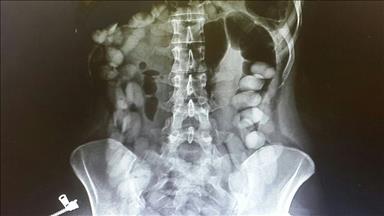

Recep Çeşmeci (31), halsizlik ve karın ağrısı şikayetiyle Konya Farabi Hastanesi'ne başvurdu. Burada yapılan kontrollerde Çeşmeci'nin bağırsağında parazit olduğu belirlendi.

Gerçekleştirilen operasyonla Çeşmeci'nin bağırsağından 2,5 metre boyunda yassı solucan çıkarıldı.

Bunun üzerine yapılan kontroller sonrası hastanın ince bağırsağından 2,5 metre uzunluğunda yassı solucan çıkarttıklarını ifade eden Erenoğlu, ''Muhtemelen solucan, tüketilen etten oluşmuş. Bu durum hastanın bağırsağı, boşaltım sistemi ya da karaciğer-dalak gibi organlarını etkiliyordu'' dedi.